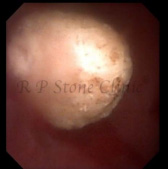

The Images Below are of Kidney Stones taken as snapshots from the video recording of RIRS Surgery done at our hospital with Digital Flexible Ureteroscopes, Flex XC and Flex XC S.